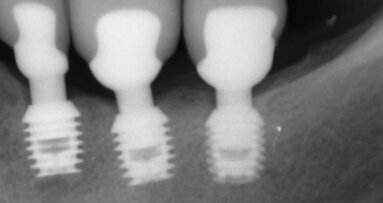

Negli ultimi anni, l’uso frequente di materiali di restauro dentali shade-matched e radiopachi atti a sostituire la struttura cariosa dei denti dopo la preparazione della cavità ha portato ad un aumento significativo delle lesioni cariose secondarie. Lo scarso adattamento dei materiali a legarsi alla struttura dentale consente ai fluidi e all’acido batterico di sfuggire, con conseguente demineralizzazione della struttura dentale sotto l’otturazione e la formazione di carie secondarie.

I risultati dello studio hanno dimostrato che l’imaging SWIR ha superato l’imaging termico complessivo nelle analisi delle lesioni cariose secondarie sulle superfici coronali. L’imaging termico ha funzionato bene nell’identificare le fessure, cioè le aree di microleakage, tra materiale composito e struttura del dente, ma talvolta ha prodotto risultati errati per quanto riguarda l’anatomia occlusale complessa e le fessure delle interfacce che tendono a trattenere l’acqua, poiché ciò ha interferito con la disidratazione termica. L’imaging SWIR è meno soggetto a tali interferenze, in quanto è in grado di distinguere materiali compositi, struttura del dente sano e lesioni con elevato contrasto. Nonostante la complessa geometria e topografia di alcune lesioni, SWIR imaging ha esaminato la permeabilità con quasi la stessa precisione del OCT.